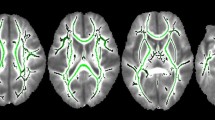

Data analysis

SPM was used for pre-processing of the resting state functional imaging data. The functional image series were corrected for head motion by realigning all images to the mean of all functional volumes. Although the neonates were asleep during the fMRI procedures, head motion was still problematic and was corrected as described in detail in the section below. The mean functional image was co-registered to a corresponding T2-weighted high-resolution image. T2-weighted images were segmented into gray matter, white matter, and cerebrospinal fluid (CSF) using the UNC neonatal tissue probability maps (Shi et al. 2010a, b). Tools developed for segmentation of adult brain images do not work as well in neonatal brain images due to reduced contrast between gray matter and white matter that arises from the higher water content and limited myelination in the neonatal brain. Consequently, we utilized a neonatal brain atlas developed specifically to address this low contrast condition by introducing age appropriate prior probability estimates (Shi et al. 2010a, b). As a final step, the images were normalized to the neonatal template (Shi et al. 2011), re-sliced to a voxel size 2 × 2 × 2 mm, and smoothed with a full width at half maximum (FWHM) Gaussian Smoothing kernel of 6 mm. T1-weighted images in neonates do not provide sufficient contrast for segmentation and corregistration and were not used in our analysis.

Following these temporal preprocessing steps, an ROI-to-ROI functional connectivity analysis was performed by grouping voxels into the 90 ROIs defined specifically for the neonatal brain. These 90 ROIs are defined objectively using a neonatal brain image atlas, neonate.aal (automated anatomical labeling) (Shi et al. 2011). The correlation matrix among these ROIs is then estimated for each subject by computing Pearson’s correlation coefficients between each ROI time-series and the time-series of all other ROIs. The correlation values for each subject were Fisher transformed to normally distributed scores and used in subsequent analysis.